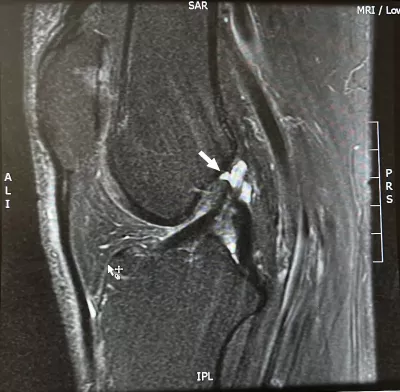

An MRI confirmed what I suspected: I tore my medial collateral ligament (MCL) in my ski accident. But it also showed what I'd hoped it wouldn't: My anterior cruciate ligament (ACL) was completely ruptured. Not only that, but I had a complex tear of the medial meniscus.

He walks me through the MRI. "These look like chronic injuries, not acute," he says. "They don't look how we'd expect them to if they had occurred when you had your ski accident. We'll never know for sure, but it's likely that most of what we're seeing was already there."

OK, that's a surprise. I had assumed I already had some ligament damage from a wallyball injury 15 years ago, but I'd thought it was my posterior cruciate ligament (PCL). Oh, and there was that yoga injury where the instructor (notorious for his forceful approach) stood and bounced on my knees to push them to the floor. That, and a bunch of other knee-things in my 62 active years, might explain what we were seeing. And if I've been doing OK with those this long, maybe I don't need surgery now.

What about my torn meniscus? Won't it need surgery? It's likely it was also already torn when I had my ski accident. Acute injuries tend to produce simple meniscal tears, but complex tears like mine are usually due to age-related wear and tear (so to speak). And, given what I am able to do (I do brag a little about my recent ski day), he didn't consider me a candidate for meniscal surgery.